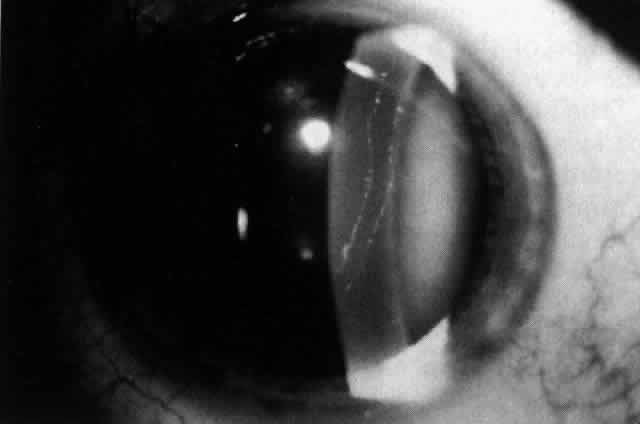

The corneal abnormalities are the most characteristic and the most varied. Lesions at Descemets membrane may take the form of individual or groups of vesicular-appearing lesions; bandlike lesions with scalloped, irregular edges (Fig. 4); or islands of abnormal-appearing endothelial cells. By specular microscopy, these areas consist of abnormal enlarged or irregularly shaped cells or black acellular zones.23 Areas of thickening of Descemet's membrane may occur, with involvement ranging from small areas to the entire posterior corneal surface.21,22

Fig. 4. Typical bandlike lesion with irregular, thickened margins at the level of Descemet's membrane and endothelium in a patient with posterior polymorphous corneal dystrophy.